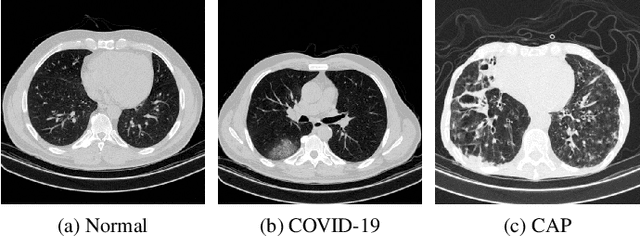

Abstract:We propose a two-stage Convolutional Neural Network (CNN) based classification framework for detecting COVID-19 and Community-Acquired Pneumonia (CAP) using the chest Computed Tomography (CT) scan images. In the first stage, an infection - COVID-19 or CAP, is detected using a pre-trained DenseNet architecture. Then, in the second stage, a fine-grained three-way classification is done using EfficientNet architecture. The proposed COVID+CAP-CNN framework achieved a slice-level classification accuracy of over 94% at identifying COVID-19 and CAP. Further, the proposed framework has the potential to be an initial screening tool for differential diagnosis of COVID-19 and CAP, achieving a validation accuracy of over 89.3% at the finer three-way COVID-19, CAP, and healthy classification. Within the IEEE ICASSP 2021 Signal Processing Grand Challenge (SPGC) on COVID-19 Diagnosis, our proposed two-stage classification framework achieved an overall accuracy of 90% and sensitivity of .857, .9, and .942 at distinguishing COVID-19, CAP, and normal individuals respectively, to rank first in the evaluation. Code and model weights are available at https://github.com/shubhamchaudhary2015/ct_covid19_cap_cnn